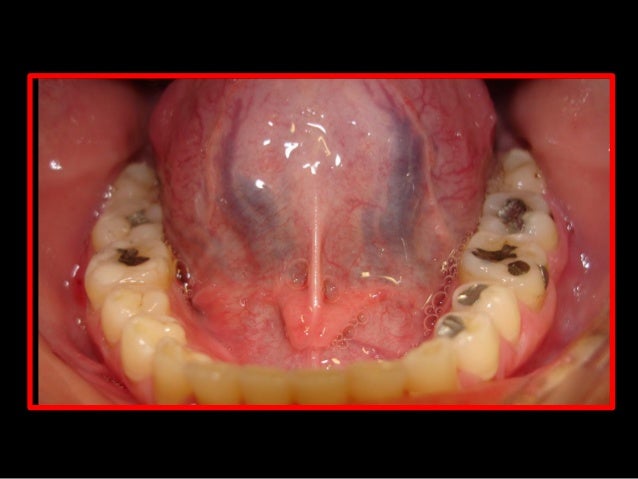

29. 29. Radiografia Periapical Início do Tratamento Após 11 meses de Tratamento

Em uma oclusão fisiológica ou orgânica, no final do fechamento mandibular, a ação dos músculos elevadores promove o assentamento dos côndilos nas fossas mandibulares do osso temporal, denominado posição de relação cêntrica (RC), coincidente com o máximo de contatos dentários posteriores bilateral, denominado máxima intercuspidação (MI) ou oclusão dentária. Como resultado a mandíbula assume posição estável denominada oclusão em relação cêntrica (ORC), na dimensão vertical de oclusão (DVO). Em seguida o relaxamento dos músculos elevadores gera a dimensão vertical de repouso (DVR).